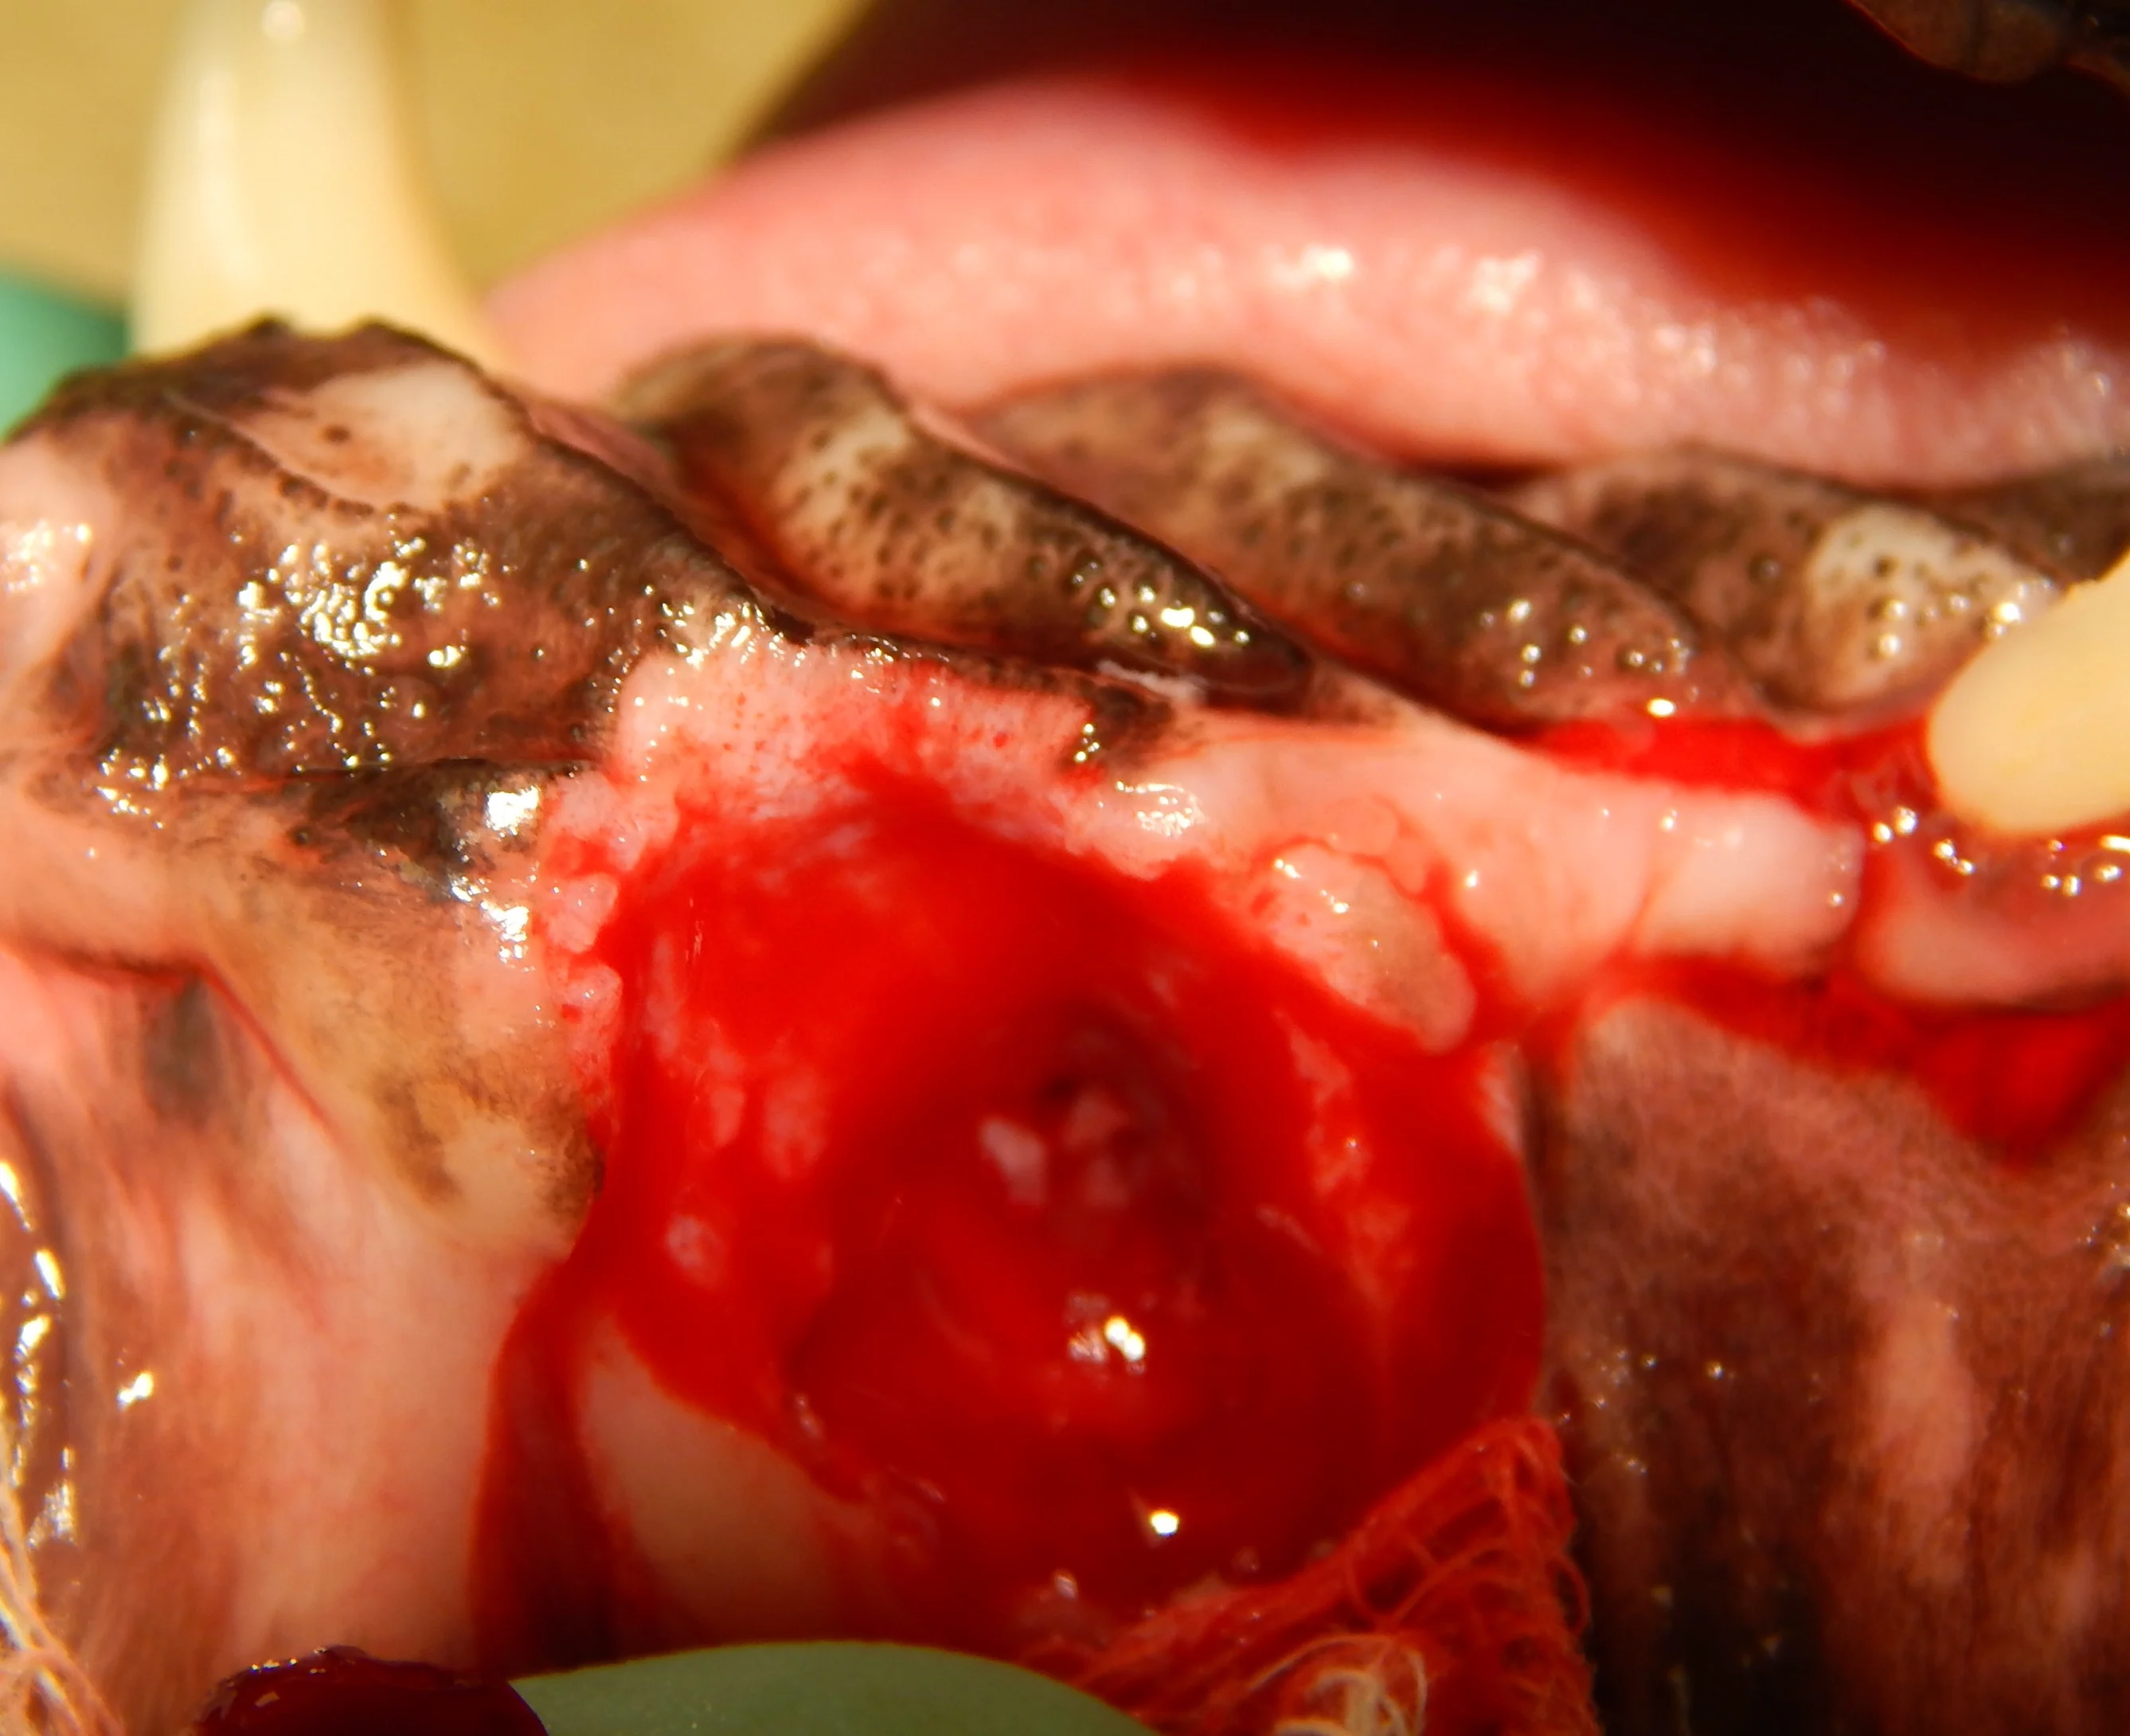

Oronasal fistulas may often be present prior to surgical extraction of maxillary teeth (Figures 6 and 7) but can also be a result of the surgical procedure. Although any maxillary tooth extraction can result in an oronasal fistula, it is most common following extraction of a maxillary canine tooth. Inadequate healing may lead to chronic oronasal fistulation (Figure 8). The quality of the tissue used to close the fistula and lack of wound tension are especially important in closure of oronasal fistulas. Development of a healthy recipient bed for the flap (Figure 9) and use of an Elizabethan collar to prevent self-trauma by the patient can also reduce flap failure.4

A chronic oronasal fistula (arrow) at the extraction site of the right maxillary canine tooth. Foreign material can be seen in the nasal cavity.

A coarse cylindrical diamond bur used to create a recipient bed (A). Removal of the epithelium allows improved healing of the sutured mucogingival flap (B).